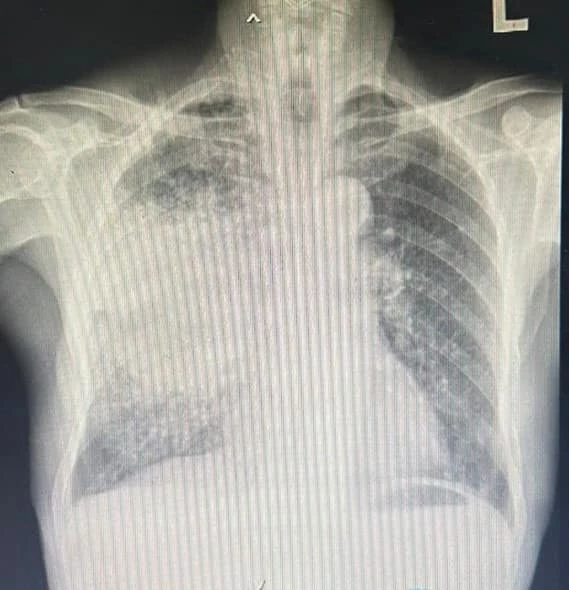

จากการเปรียบเทียบอัตราการตายของผู้ป่วยโรคมะเร็งปอด ตั้งแต่ปี 2553-2564 ระหว่าง ภาคเหนือ ภาคอีสาน และภาคใต้ พบว่า ภาคเหนือ โดยเฉพาะจังหวัดเชียงใหม่ และลำปาง มีอัตราการเสียชีวิตด้วย โรคมะเร็งปอดสูงที่สุด

นอกจากนี้ยังพบ สัดส่วนของผู้ป่วยมะเร็งปอดในคนหนุ่มสาวของประชากรภาคเหนือสูงกว่าภาคอื่นๆ ซึ่งน่าจะมีความเกี่ยวข้องกับฝุ่น PM2.5

เนื่องจากมีงานวิจัยที่รองรับทั่วโลกแล้วว่า การสัมผัสฝุ่น PM 2.5 ในระยะยาว มีความเสี่ยงต่อการเกิดโรคมะเร็ง โดยเฉพาะอย่างยิ่ง มะเร็งปอด ได้อย่างมีนัยสำคัญ

แต่โรคที่มีความรุนแรง ซึ่งมีความสัมพันธ์กับปริมาณฝุ่น PM2.5 และพบมากที่สุดในเดือนมีนาคม 2567 คือ การกำเริบของโรคถุงลมโป่งพอง โรคหลอดเลือดหัวใจและ โรคหลอดเลือดสมอง ซึ่งทั้งหมดนำไปสู่การเจ็บป่วยที่รุนแรงจนถึงขั้นเสียชีวิต